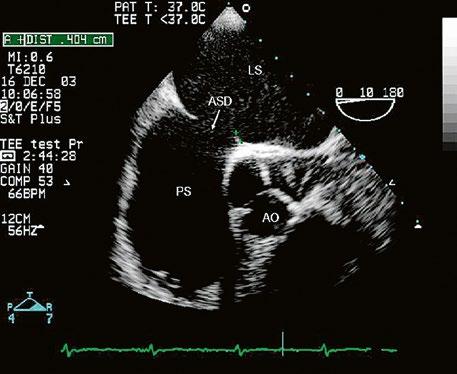

Obr. 45.3 Defekt septa síní typu sinus venosus superior, TEE nad úrovní aortální chlopně, defekt je v horní části septa označen křížky

AO – aorta, LS – levá síň, PS – pravá síň

z Defekt síňového septa typu sinus venosus superior: 9 %, v místě vústění horní duté žíly (HDŽ), která na defekt nasedá, téměř vždy je spojen s parciálním anomálním návratem pravostranných plicních žil do HDŽ nebo do pravé síně (kap. 45.18 Anomální návrat plicních žil (Obr. 45.3, Obr. 45.4, Video 45.3, Video 45.4).